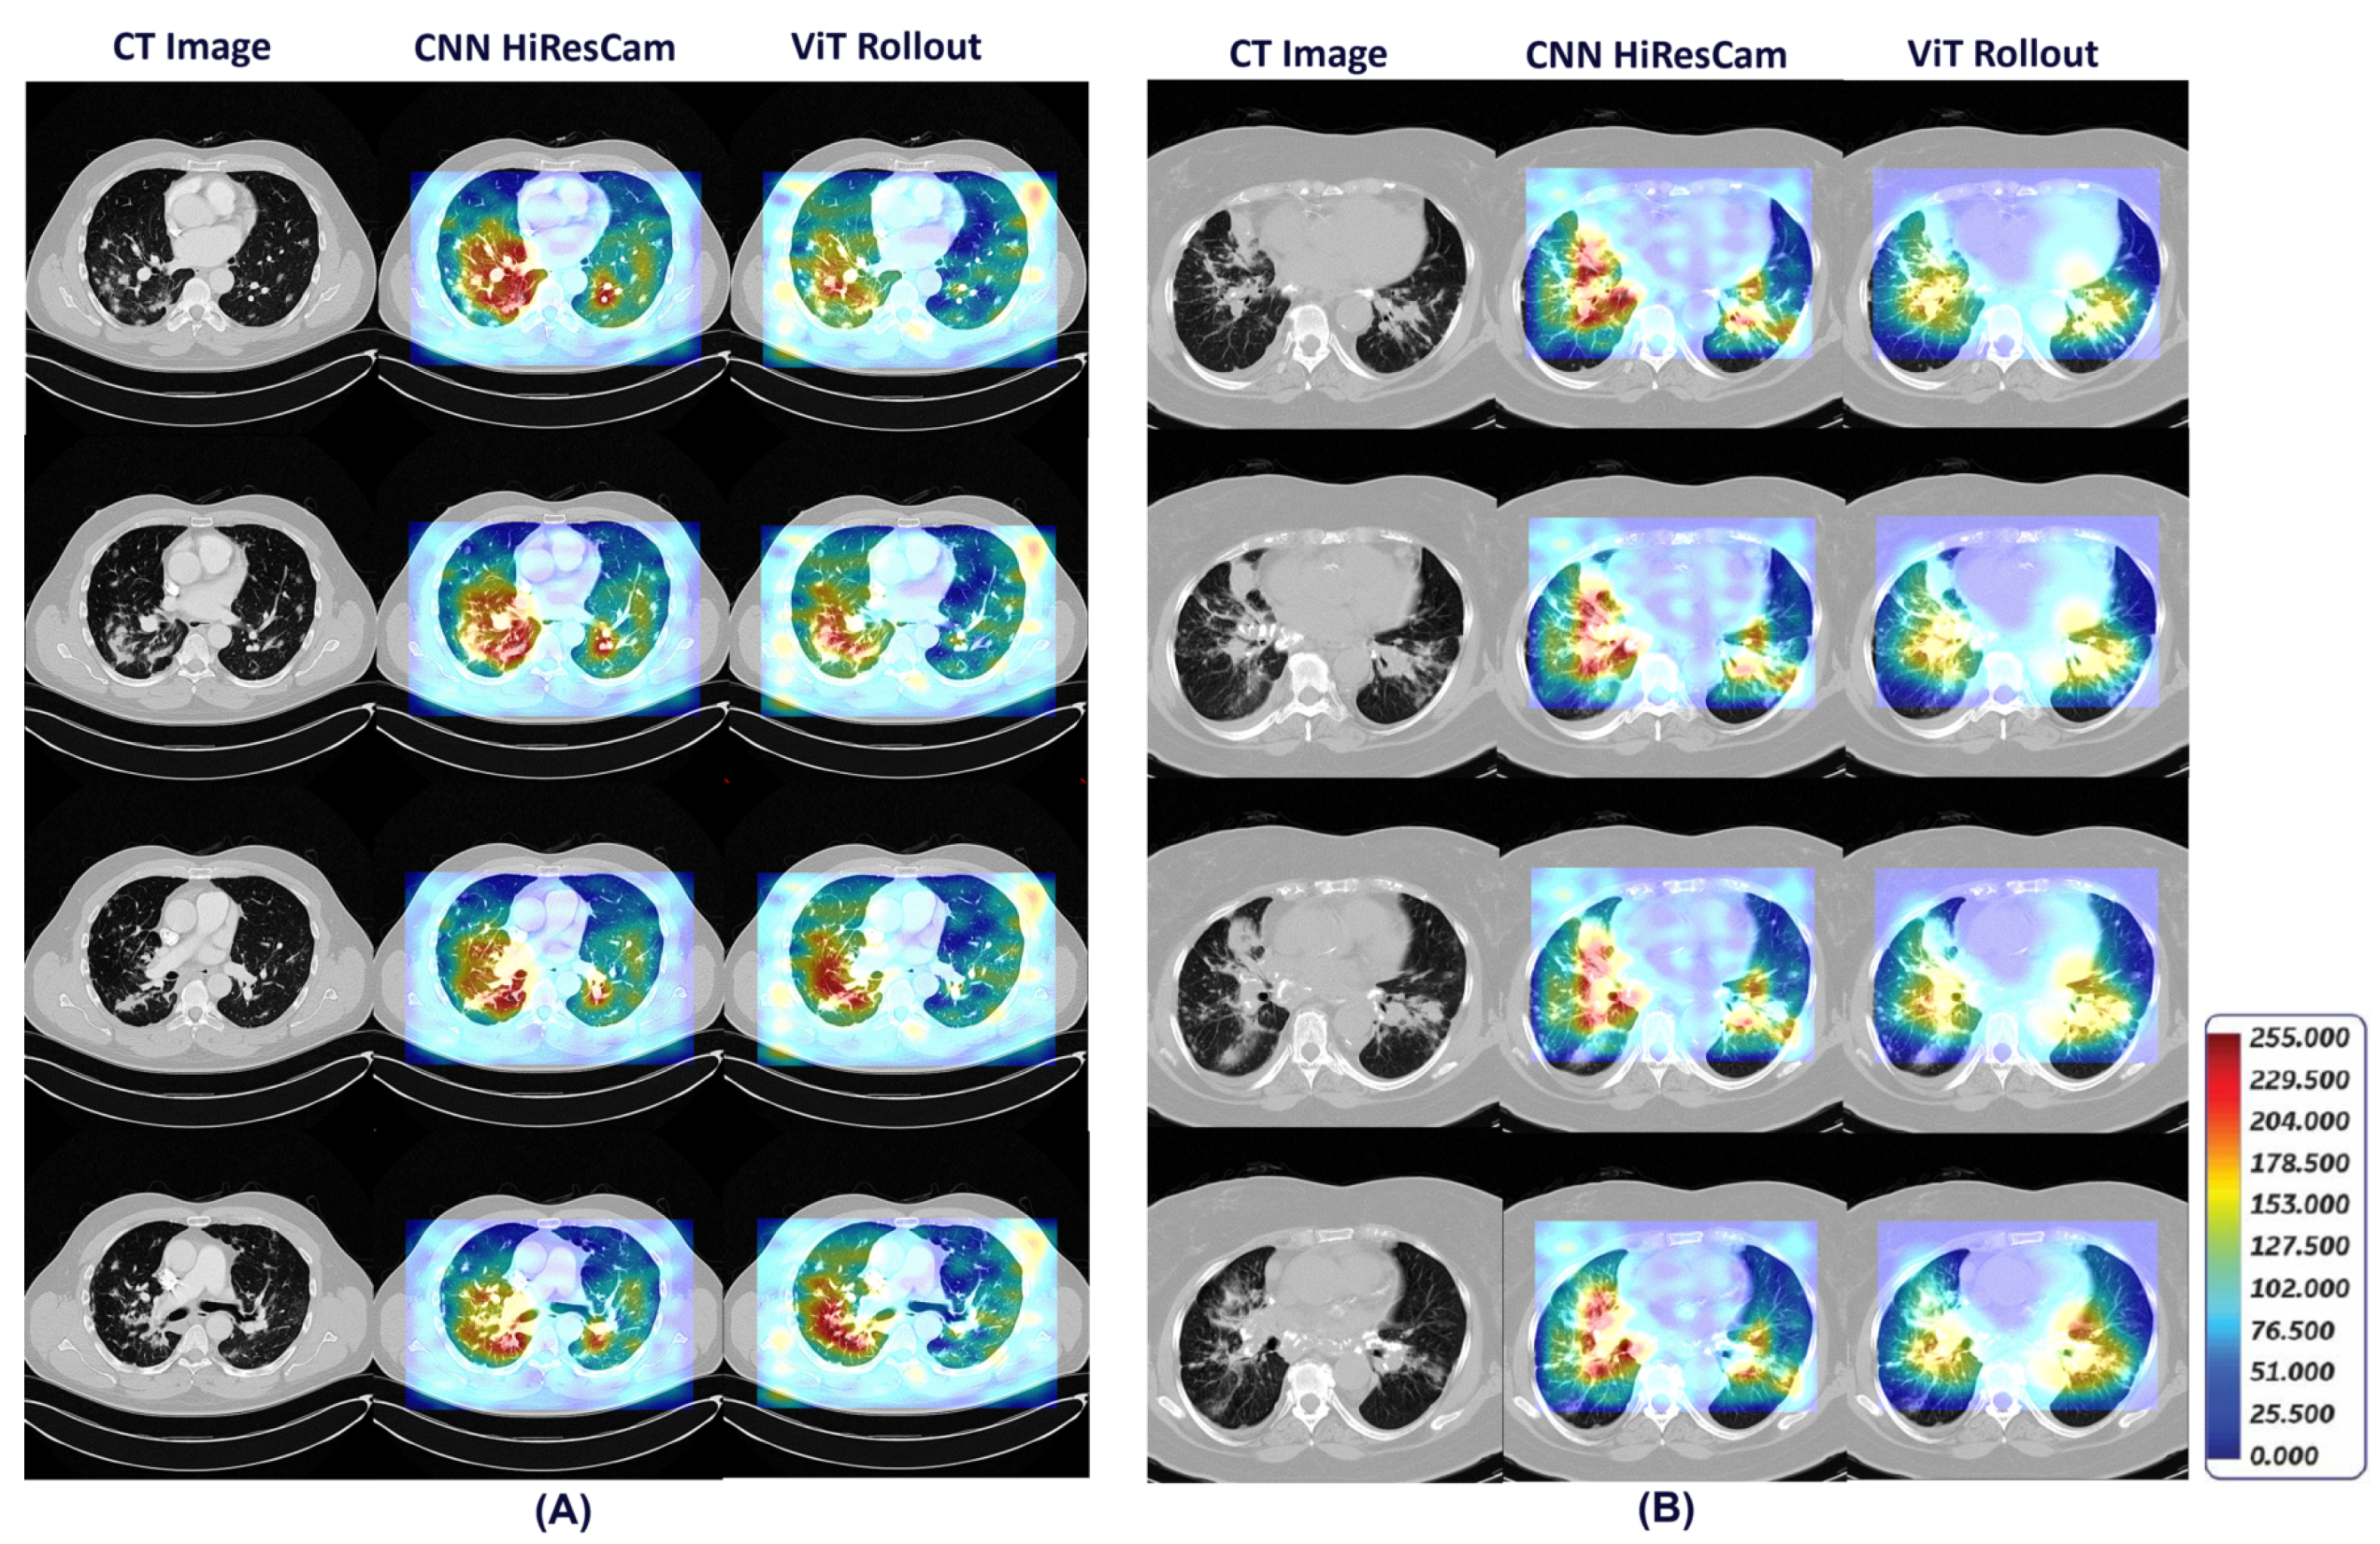

- Our framework also provides visual explainability for the classification of pulmonary sarcoidosis vs. lung malignancies (LCa) that suggests regions of interest that are considered important by the network for making the prediction.

2.3. Generating Visual Explanations for Predictions

- Draelos, R.L.; Carin, L. Hirescam: Faithful location representation in visual attention for explainable 3d medical image classification. arXiv 2020, arXiv:2011.08891. [Google Scholar]

- Abnar, S.; Zuidema, W. Quantifying attention flow in transformers. arXiv 2020, arXiv:2005.00928. [Google Scholar]